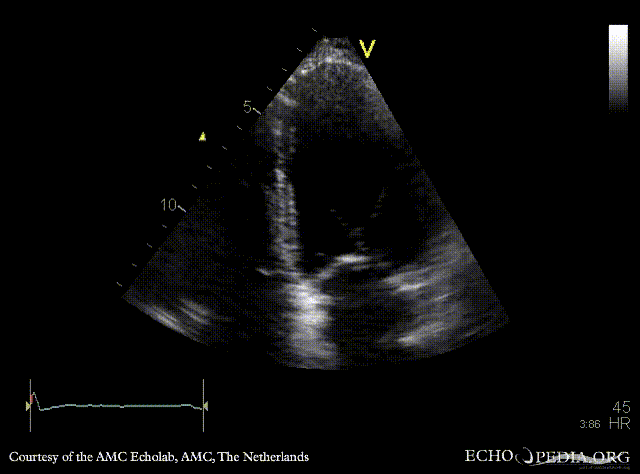

| Courtesy of: AMC Echolab, AMC, The Netherlands | |

| A4CH: apical akinesia | A2CH |